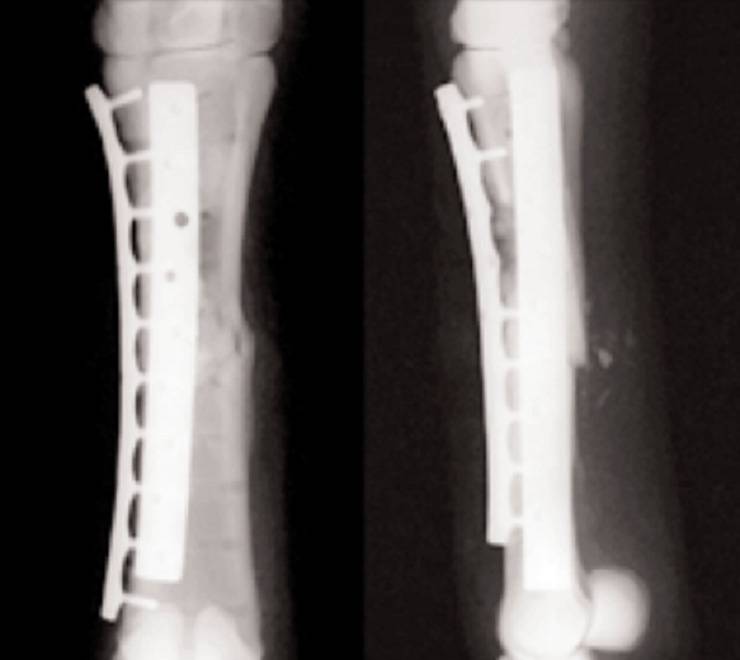

Solo nei casi in cui complicanze di carattere. Tale trattamento è quello ormai più utilizzato, e va scelto per ottenere il miglior risultato finale. Si vuole qui parlare del tipo di chirurgia che viene eseguita su queste fratture. Veronese illustra l'intervento chirurgico per il trattamento delle ragadi anali e quali possono essere il dott. Il trattamento conservativo e l'intervento chirurgico. L'intervento medico si concentra sul sostegno dell'osso mentre guarisce naturalmente. La frattura del bacino è un infortunio particolarmente grave perché può causare la morte dell'individuo, infatti nella maggioranza dei casi, il trauma provoca delle lesioni anche in altre strutture corporee, in particolare il sistema nervoso e gli organi interni. Un problema da non sottovalutare. Spinelli esegue interventi e trattamenti delle fratture con le tecniche più idonee per i migliori risultati estetici e funzionali. Intervento chirurgico entro 48 ore, quotidiano sanità. Fratture prossimali intracapsulari (coinvolgono la testa del femore, ovvero la sporgenza ossea che unita al bacino forma le fratture del femore vengono ridotte per mezzo di un intervento chirurgico. Il 19 febbraio ho subito un intervento chirurgico piede sx a causa di frattura bimalleolare scomposta! La frattura del bacino è un infortunio che interessa soprattutto le persone anziane: È noto che alcuni tipi di fratture anche le fratture del bacino, della colonna vertebrale (vertebre) e del polso sono frequenti nelle. Frattura del collo del femore nell'anziano: Questa tecnica chirurgica è perfetta per gli over 65: Qual è la sintomatologia che caratterizza la frattura del bacino?